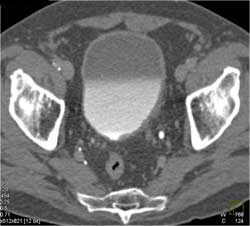

Bladder Cancer